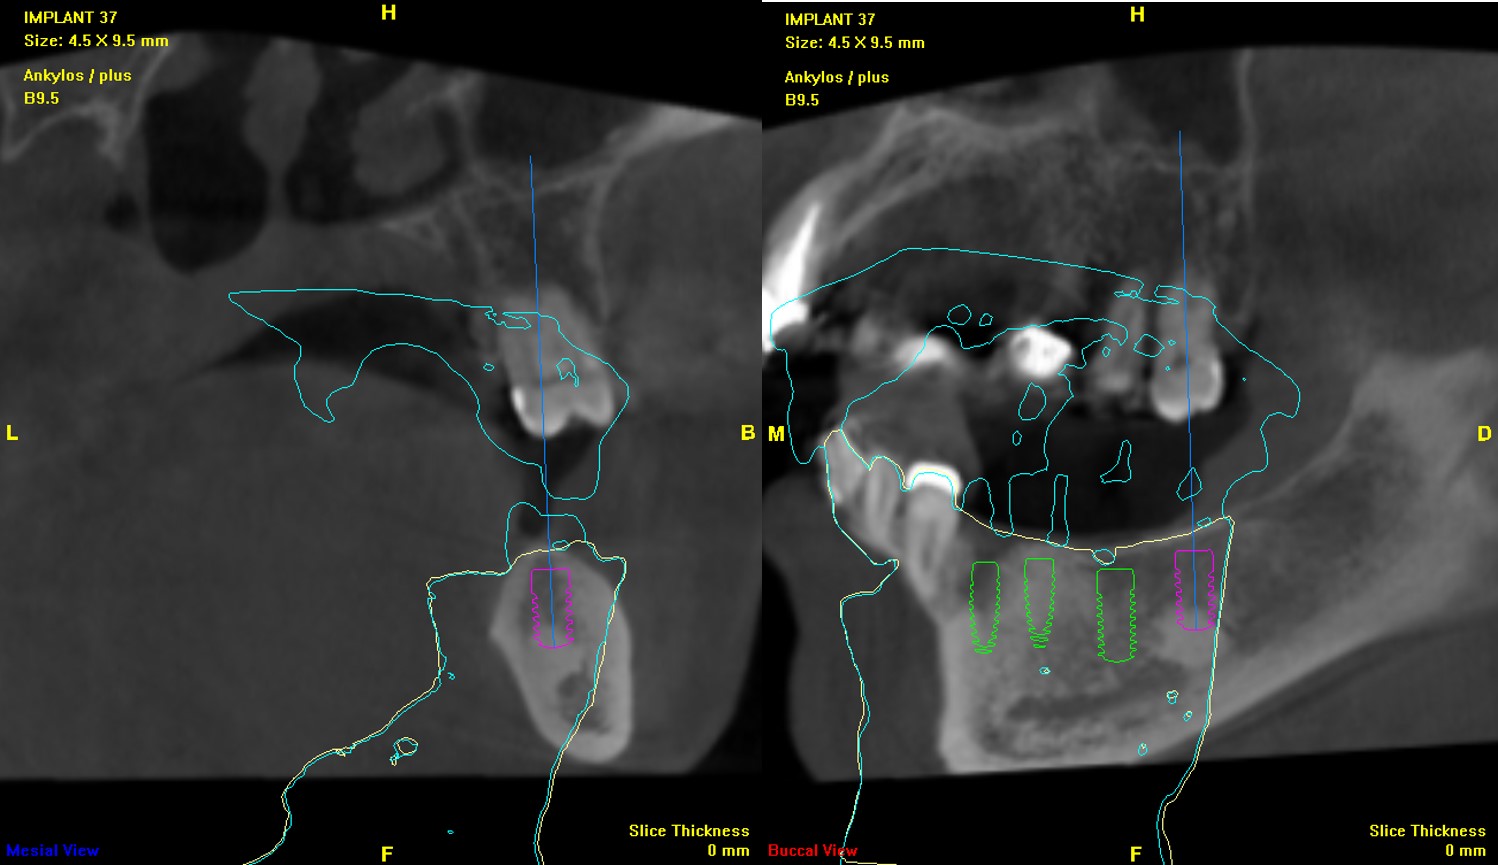

植體位分析:#35

植體位分析:#36

植體位分析:#37